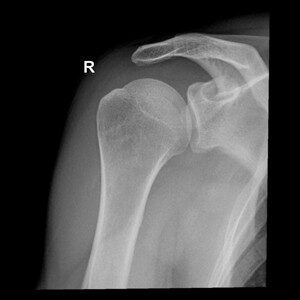

Praxisnahe Röntgenfälle, strukturierte Befundung, fundiertes Fachwissen. Lernen, üben, anwenden — mit echten Fällen aus der klinischen Praxis.

Die spezialisierte Lernplattform für Projektionsradiographie. Im Mitgliederbereich steht eine stetig wachsende Fallsammlung mit realen Röntgenbildern zur Verfügung — systematisch aufgebaut, mit strukturierter Befundung, Befundcheck und klinisch relevanten Zusatzhinweisen.